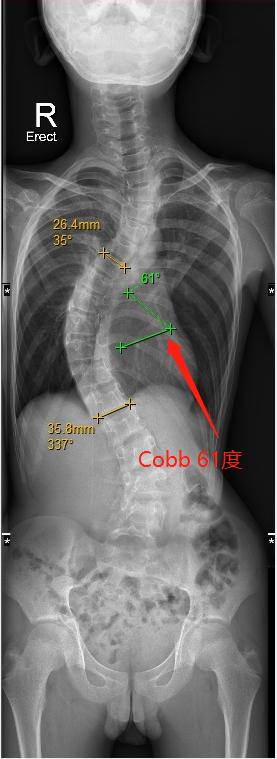

港大深圳医院脊柱外科主任、“三名工程”团队领军人张文智教授介绍,小磊曾使用过支具矫正脊柱,但效果并不理想。“小磊来到港大深圳医院治疗时,Cobb角已经达到了61度,远超过45度的手术干预指标,呈明显S形状,已经压迫到了心肺等主要器官。考虑到他的病情可能的恶化发展和手术预后,我们建议小磊立即进行手术干预。”

小磊手术前评估(左图),Cobb角度为61度,术后(右图)约为30度

在张文智教授团队及多学科共同合作下,小磊于5月3日进行了手术,手术时长约3小时,Cobb角由术前61度矫正为30度,手术进行得非常成功,“后续小磊只需要每2-3个月定期复诊一次即可。预计在植入的1-2个月后可撑开钛棒,并在未来三年内定期通过仪器进行体外拉伸,调整钛棒长度及脊柱角度,直到基本痊愈。”